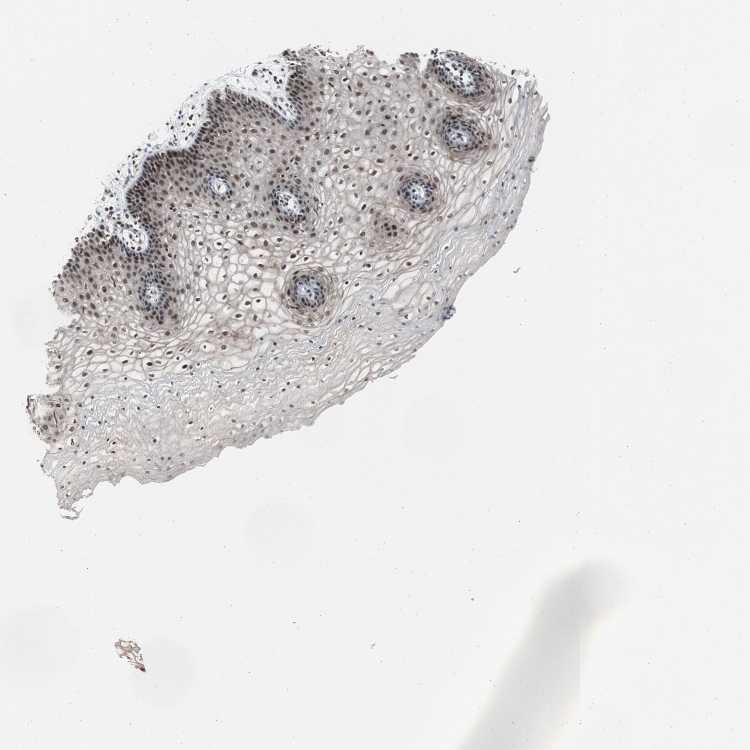

VAGINA - Antibody stainingi

Antibody staining in the annotated cell types in the current human tissue is reported as not detected, low, medium, or high, based on conventional immunohistochemistry profiling in selected tissues. This score is based on the combination of the staining intensity and fraction of stained cells.

Each image is clickable and will lead to virtual microscopy that enables deeper exploration of all samples and also displays staining intensity scores, fraction scores and subcellular localization as well as patient and tissue information for each sample.

Antibody HPA006914

Squamous epithelial cells High